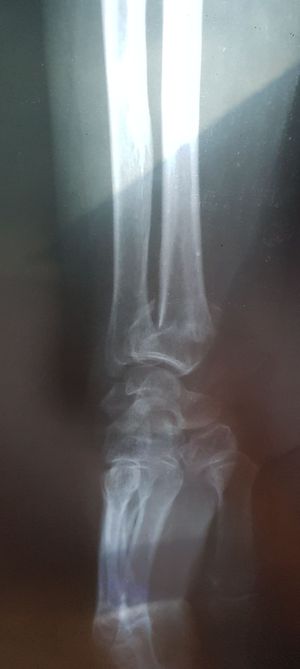

Colles fracture

Fractures

Orthopedicsurgery

Radius

Radial fracture